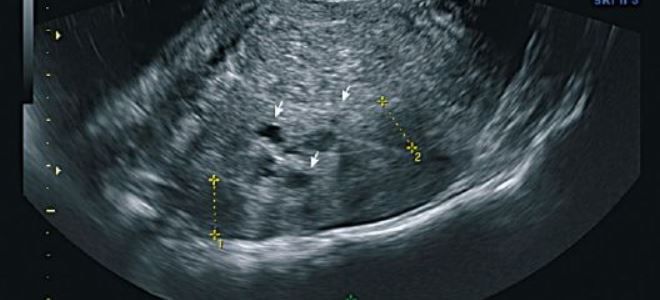

| Диагностика | Гинекологический осмотр, УЗИ органов малого таза, МРТ, лапароскопия (золотой стандарт). | Диагностика необходима для выбора адекватного лечения. |